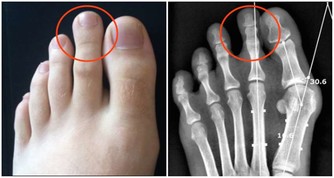

痛風,幾乎也是讓大家聞之色變的一類疾病了,因為一旦患上了痛風,不僅身體會長時間受到折磨,精神上也會感到十分痛苦,而且在痛風患者的日常生活中,稍有不慎就可能會導致其他病症一齊發作。

所以,對於痛風,大家一定要有相關的防範意識,不要等到疾病纏身了,才知道後悔,尤其是平時在飲食中經常攝入高嘌呤食物,且尿酸水平持續偏高的人,更是要注意預防。